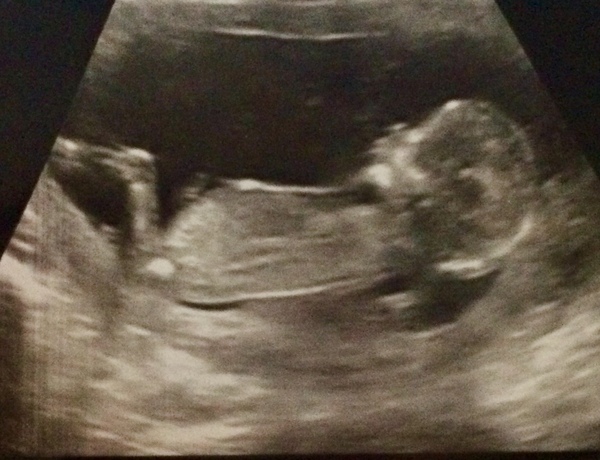

14 weeks today :) we aren’t going to find out the gender ... buying all natural and penguin themed bits in the sales... however my scan on Xmas eve has changed a lot in 6 days... has an inclination it’s a little boy 🥰